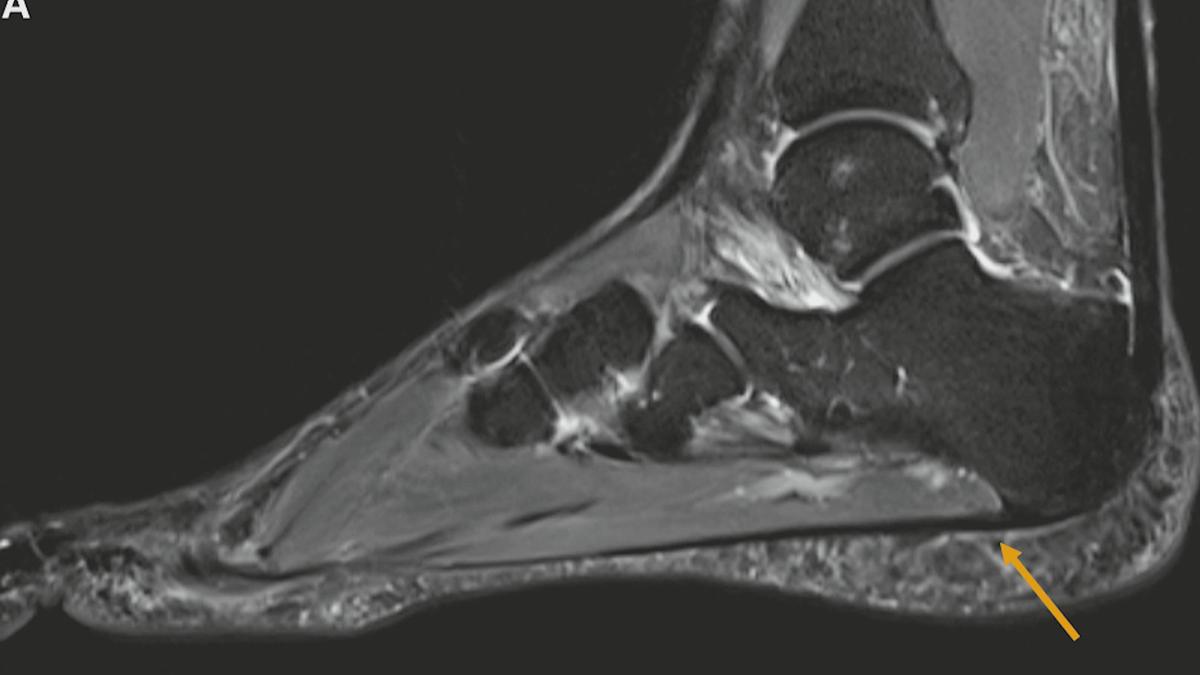

Baxter Neuropathie – ein kleiner Nerv unter Druck

Oftmals wird ein „Fersensporn“ diagnostiziert. Werden die Beschwerden, trotz Ausschöpfung aller Therapiemethoden, nicht besser, kann zusätzlich der „Baxter- Nerv“ eine Rolle spielen. Das kleine Nervenästchen gerät in 20 Prozent aller Fersensporn- Erkrankungen ebenfalls unter Druck und entzündet sich. In „Bewusst gesund“ erfahren Sie mehr zur sogenannten „Baxter - Neuropathie“ und wie sie behandelt wird.